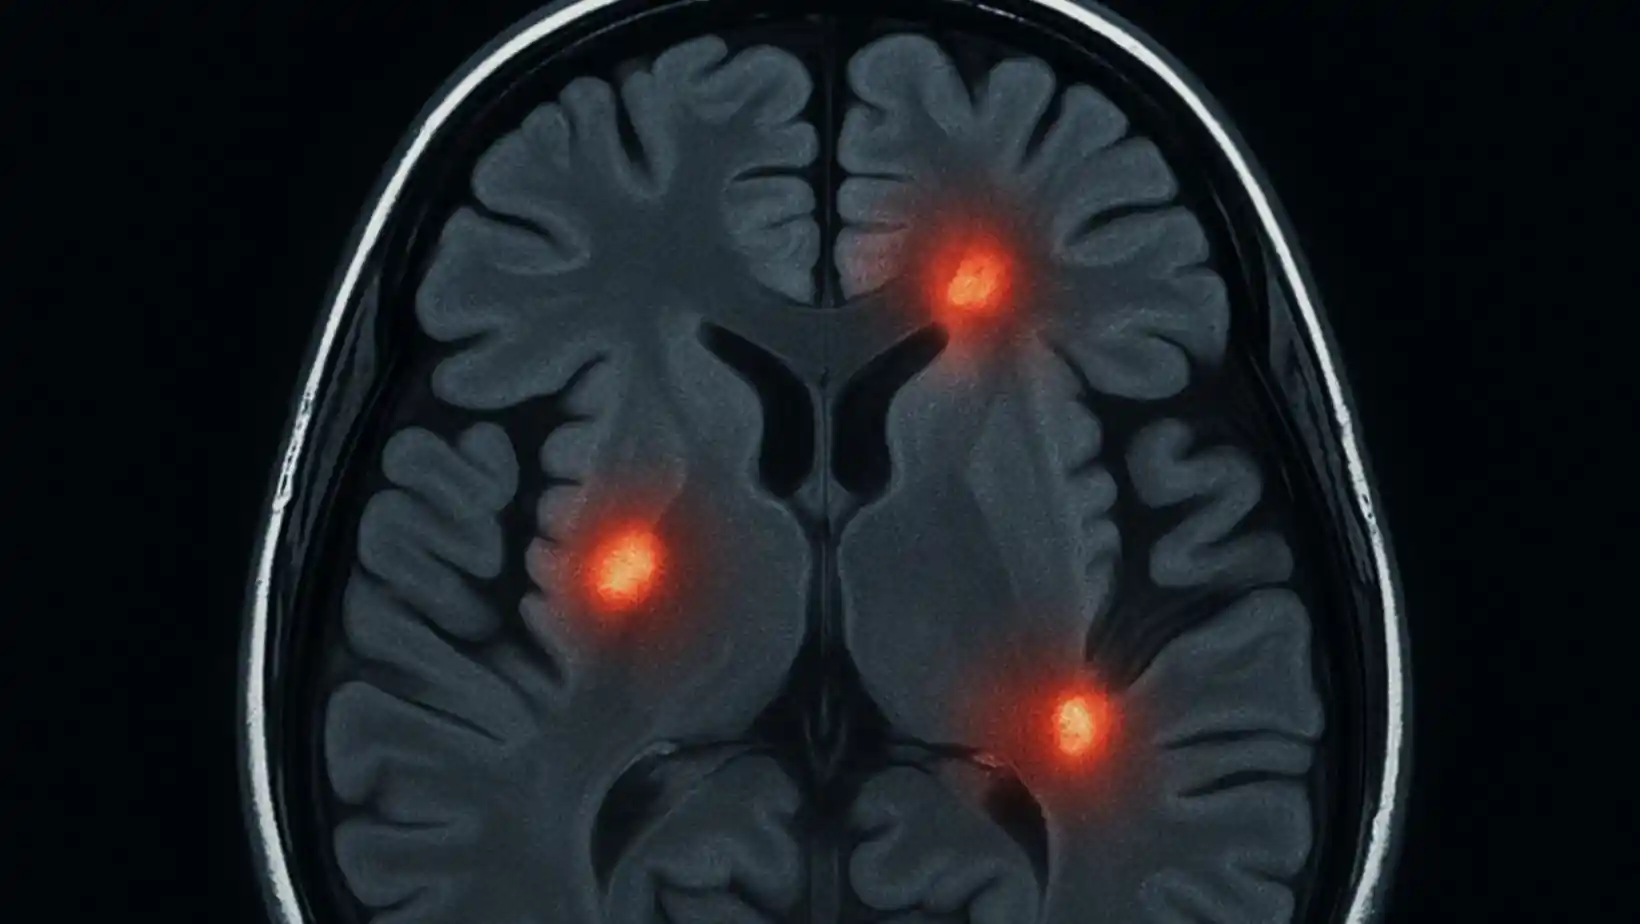

Neuroinflammation Demystified: Triggers, Symptoms, and Treatments

Neuroinflammation is the brain’s defense mechanism. When it detects a…